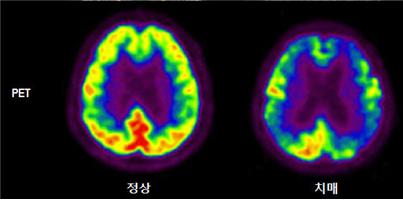

- 뇌 양전자방출단층촬영 (PET)

뇌 PET 검사는 뇌세포의 대사량을 측정하여 사진으로 표현함으로써 MRI로는 관찰할 수 없는 뇌세포의 기능적 이상을 확인할 수 있습니다. 뇌 MRI 검사로는 발견할 수 없는 치매의 최초기 병변을 찾아주는 검사입니다.